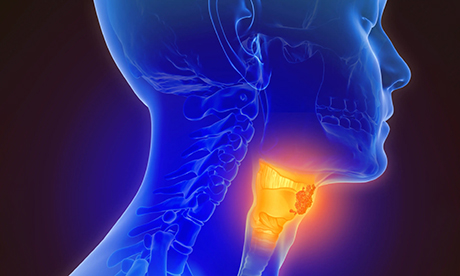

According to a recent study, oral sex has been linked to a surge in throat cancer cases, with experts saying human papillomavirus (HPV) is primarily responsible for this increase.

The study claims this has led to a rise in a particular type of throat cancer known as oropharyngeal cancer, which affects the area of the tonsils and back of the throat.

The virus can cause an HPV infection at the back of the throat or near the tonsils, which may lead to cancer. These infections usually go away on their own but, in some cases, they can persist and cause cancer.

Throat cancer diagnoses are on the rise in the UK, with around 8,300 people diagnosed yearly. This makes it the most common cancer after cervical cancer.